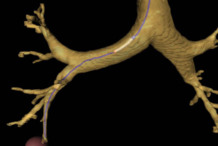

Patentan un sistema de guiado en la broncoscopia virtual para ayudar en el diagnóstico de cáncer de pulmón 05/10/2012Un equipo formado por investigadores del Instituto de Organización y Control de Sistemas Industriales (IOC) de la Universidad Politécnica de Catalunya -BarcelonaTech (UPC) y del grupo de investigación en Neumología del Instituto de Investigación Biomédica de Bellvitge (IDIBELL) ha diseñado y patentado un nuevo sistema para mejorar la exploración endoscópica de lesiones pulmonares periféricas, a partir de una sustancial mejora de las broncoscopias virtuales. Estas lesiones son los nódulos más pequeños situados en las ramificaciones más distales de los bronquios. El sistema guía al médico indicando el camino más factible para acceder a la lesión, desde la tráquea, mediante la broncoscopia. Así evita los posibles riesgos para el paciente y exploraciones fútiles y permite decidir decidir con mayor seguridad si la broncoscopia real puede ser útil o no. En los procedimientos médicos habituales de detección del cáncer de pulmón, las broncoscopias virtuales permiten la exploración de las lesiones pulmonares a partir de la reconstrucción en 3D del árbol traqueobronquial. Una vez realizada la exploración radiológica, el médico planifica la broncoscopia real, que se hace con un broncoscopio flexible, el dispositivo médico que se utiliza con fines diagnósticos o terapéuticos y con el que se extraen muestras de tejido pulmonar para hacer su biopsia. El médico puede navegar virtualmente en las vías respiratorias con el sistema ideado por el equipo de la UPC, basado en las imágenes que proporcionan una broncoscopia virtual a partir de imágenes 2D de tomografía computarizada. El sistema es novedoso porque, a diferencia de los sistemas actuales de broncoscopia virtual, tiene en cuenta la geometría y las restricciones cinemáticas del broncoscopio. Más información AlphaGalileo